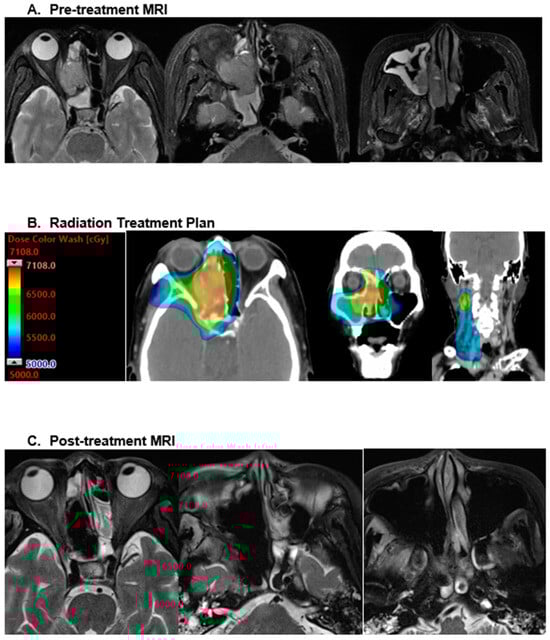

Many retrospective HNMM series reveal the consistent utilization of conventional fractionation (~2 Gy per fraction), especially in the adjuvant setting, with a well-established dose response benefit for more than 54 Gy [15]. Figure 1 demonstrates the radiation plan and subsequent treatment response following 66.01 Gy in 35 fractions to a mucosal melanoma of the right ethmoid sinus and ipsilateral neck. In addition to the common conventional schemes (60–70 Gy in 30–35 fractions), hypo-fractionation has been routinely implemented in both the definitive and palliative setting. A notable MD Anderson Cancer Center experience with MMHN utilized a hypo-fractionated regimen of 30 Gy in five fractions for oral cavity primaries, which were deemed to be a safe distance from sensitive CNS structures [16]. Subsequent data identifying improved control rates with the use of 3–4 Gy per fraction have suggested a benefit to increased biologic equivalent doses in this radioresistant histology [17,18]. Though uncommon, there are few reported uses of stereotactic body radiotherapy (SBRT) for sinonasal mucosal melanoma [19,20].

Figure 1. This figure shows the radiation plan and subsequent treatment response following 66.01 Gy in 35 fractions to a mucosal melanoma of the right ethmoid sinus and ipsilateral neck.